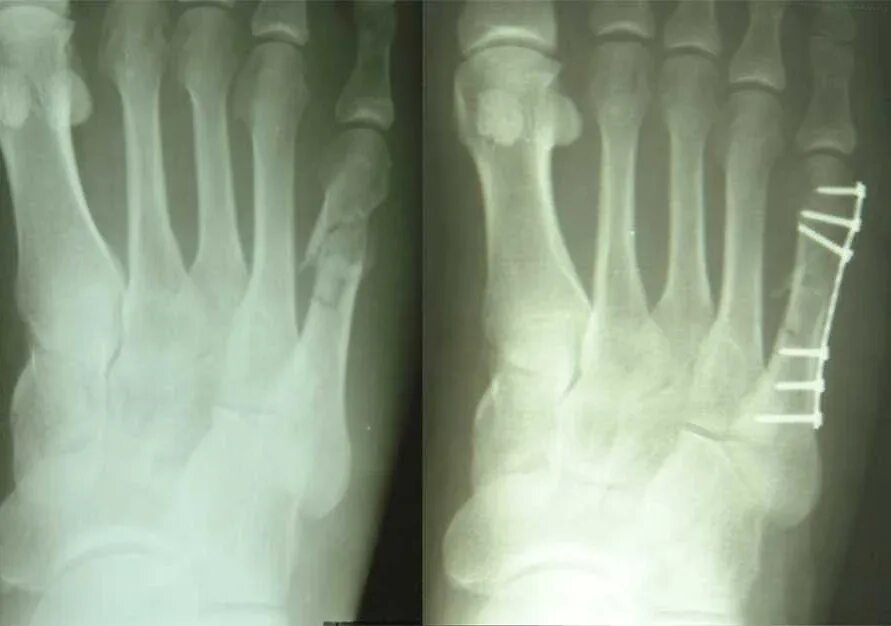

Лечить перелом стопы